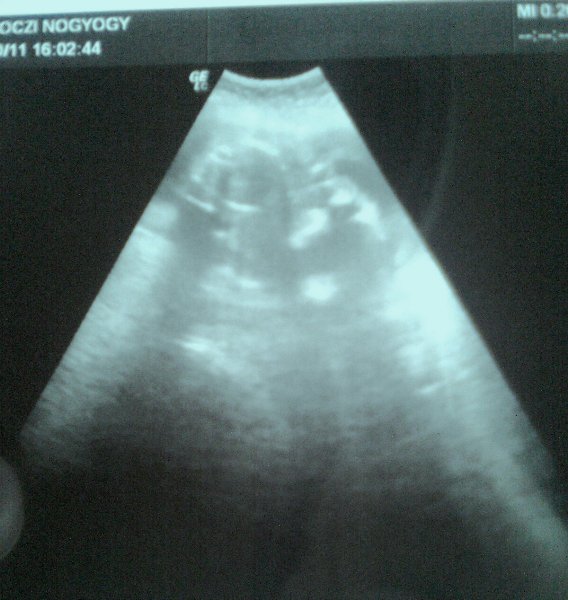

Nem voltam még 4D-n, jövő héten fogunk menni.